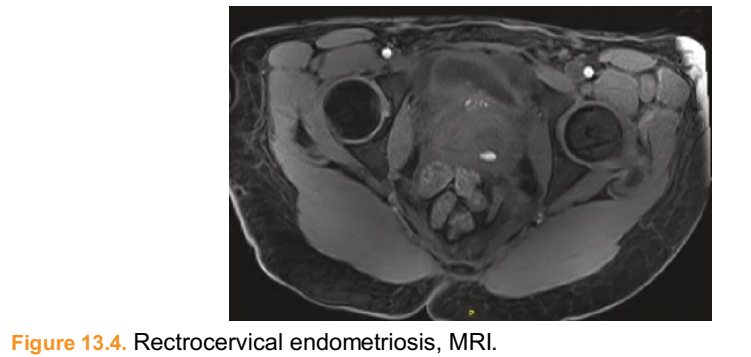

■ Computed tomography (CT) is only useful for pelvic mass evaluation and ureteral obstruction but it is not useful for pelvic soft tissue evaluation. Instead, we prefer Magnetic Resonance Imaging (MRI), with enterography, for preoperative soft tissue evaluation (Figs. 13.1 to 13.4).

Figure 13.4. Rectrocervical endometriosis, MRI.